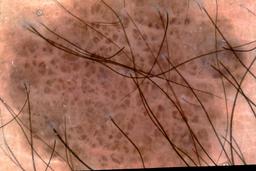

{

"age_approx": 15,

"anatom_site_general": "upper extremity",

"concomitant_biopsy": true,

"dermoscopic_type": "contact non-polarized",

"diagnosis_1": "Benign",

"diagnosis_2": "Benign melanocytic proliferations",

"diagnosis_3": "Nevus",

"diagnosis_4": "Nevus, Congenital",

"diagnosis_confirm_type": "histopathology",

"image_type": "dermoscopic",

"lesion_id": "IL_7863876",

"melanocytic": true,

"patient_id": "IP_3774474",

"sex": "male"